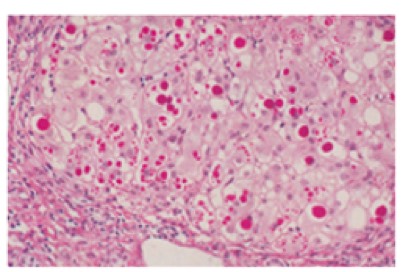

1051. Месячному ребенку поставили диагноз гепатит новорожденных, по результатам лабораторных исследований фракция конъюгированного билирубина составляет более 50% от общего билирубина, уровень сывороточной щелочной фосфатазы заметно увеличивается, выполнена биопсия печени c последующим pas-окрашиванием препарата, диагноз _____ наиболее вероятен